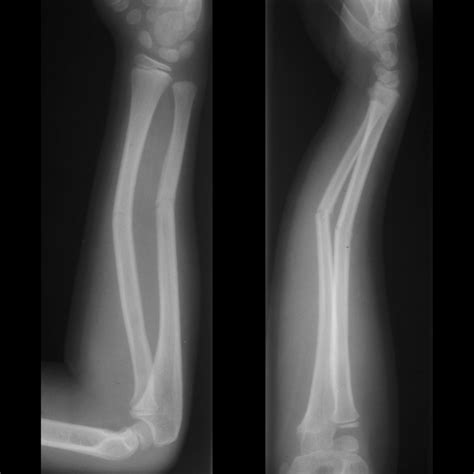

Xray Of Bone Fracture

Bone fractures are a common injury that can occur due to various reasons such as accidents, falls, or sports injuries. An accurate diagnosis is crucial for effective treatment, and one of the most reliable methods for diagnosing bone fractures is through an X-ray of bone fracture. This non-invasive imaging technique provides detailed images of the bones, helping healthcare professionals to assess the extent of the damage and plan appropriate treatment.

Bone fractures can be classified into several types based on their severity and the pattern of the break. Some common types of bone fractures include:

• Closed Fractures: These are fractures where the bone breaks but does not penetrate the skin.

• Open Fractures: Also known as compound fractures, these occur when the broken bone penetrates the skin, increasing the risk of infection.

• Comminuted Fractures: These involve the bone breaking into multiple pieces.

• Greenstick Fractures: Common in children, these fractures occur when the bone bends and breaks incompletely.

• Stress Fractures: These are small cracks in the bone that develop over time due to repetitive stress or overuse.

Interpreting X-ray images requires specialized training and expertise. Radiologists look for several key indicators when assessing an X-ray of bone fracture:

• Bone Alignment: They check if the bone fragments are properly aligned or if there is any displacement.

• Fracture Pattern: They identify the type of fracture (e.g., transverse, oblique, spiral) to understand the mechanism of injury.